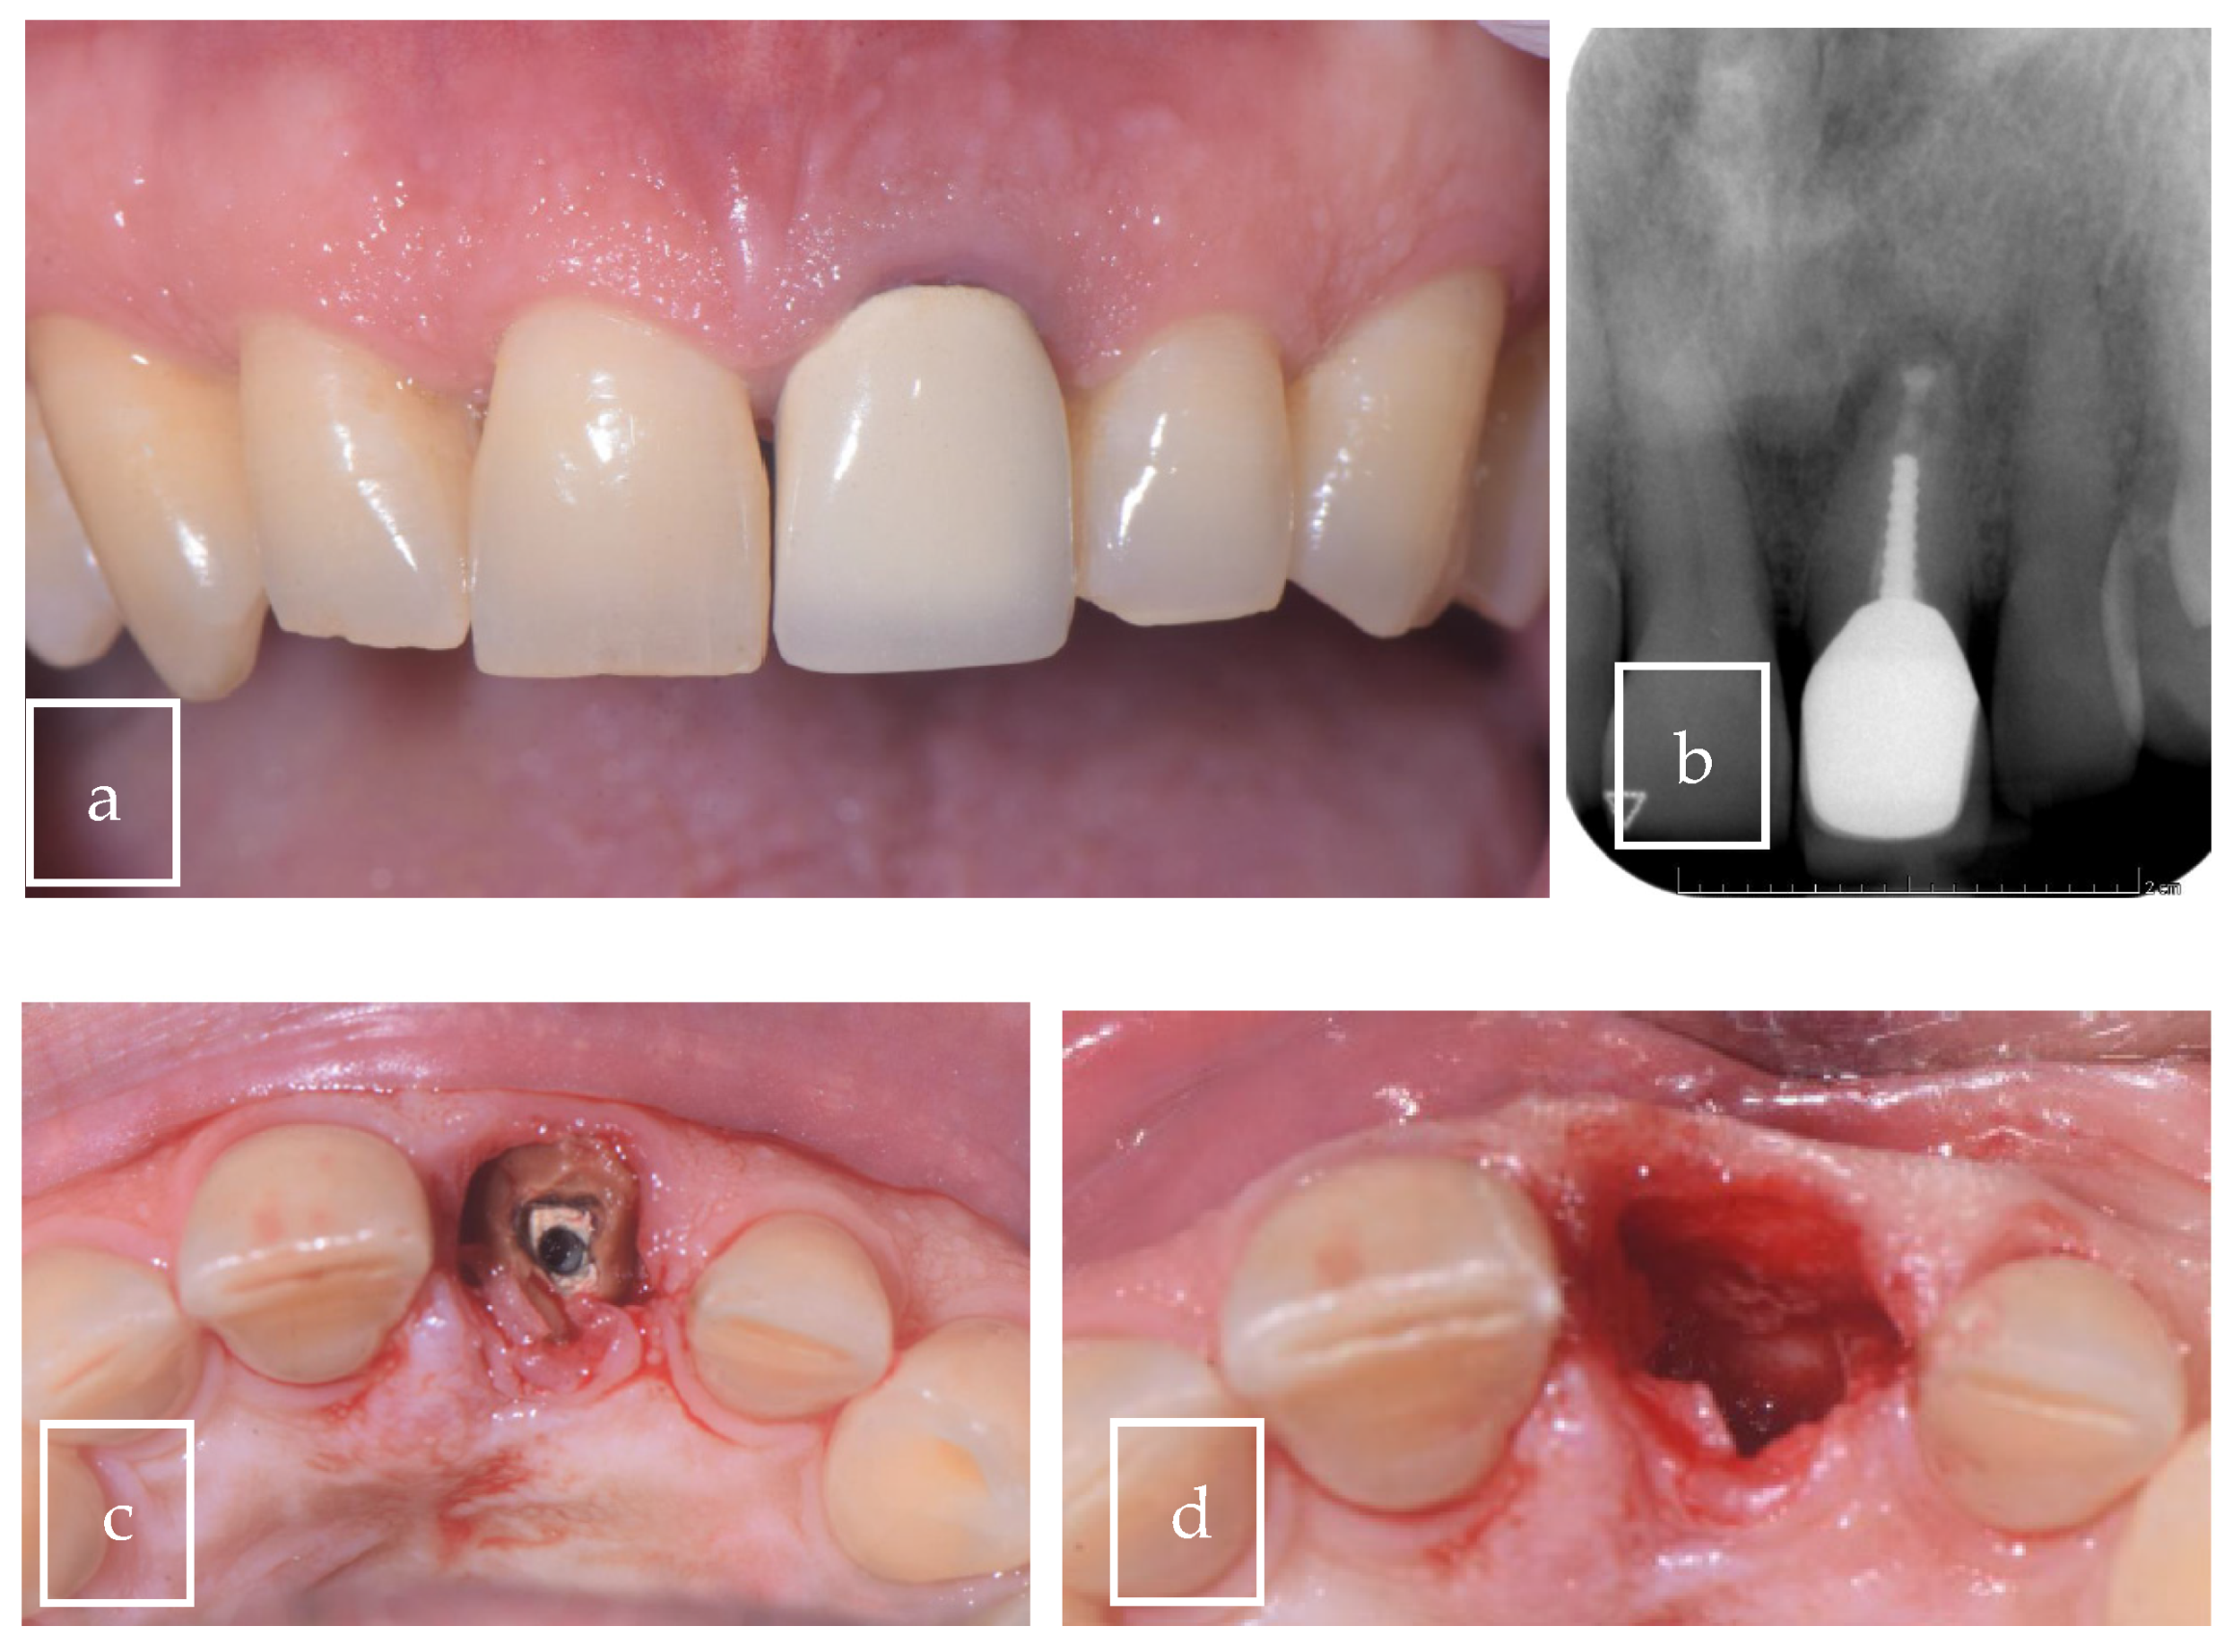

3.2. Case Presentation

| Our case | Case report | 1 | M | 63 | Asymptomatic | Right palate | Surgical excision | 9 × 8 × 12.5 mm | Radiolucent |